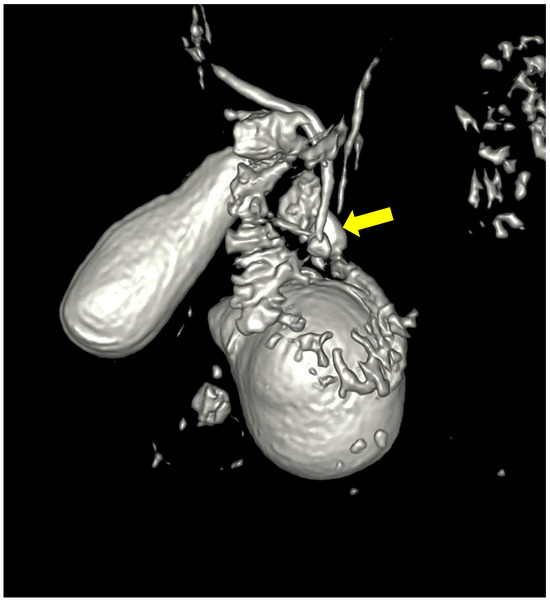

A month later, the patient was readmitted due to upper abdominal pain, a slight elevation of transaminases, alkaline phosphatase, GGT, and amylase. CRP was within a normal range, with unremarkable US/MSCT findings. The magnetic resonance imaging (MRI) demonstrated a duodenal diverticulum adjacent to the papilla, located over the junction of the common bile and pancreatic ducts, which were not dilated (Figure 3 and Figure 4).

Figure 4. Three-dimensional reconstruction showing the duodenal diverticulum near the pancreatico-billiary junction (arrow).